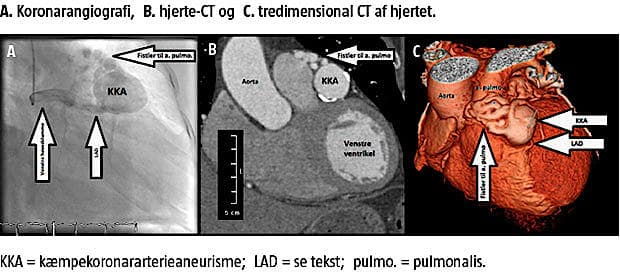

Ved KAG fandt man ingen betydende aterosklerose, men udtalt ektasi af venstre koronararteries hovedstamme og proksimale del af ramus interventricularis anterior (LAD). Ramus circumflexus (LCX) og højre koronararterie (RCA) var normale. Undersøgelsen var dog suboptimal, og den distale del af LAD kunne ikke fremstilles. Der blev derfor efterfølgende udført hjerte-CT, som ligeledes viste normale forhold i RCA og LCX, mens venstre koronararteries hovedstamme og den proksimale del af LAD var lang og ektatisk med en diameter på 8 mm. Ud for afgangen af første diagonal fandt man et anurisme med randforkalkning og en diameter på 35 mm. Fortil i anurismet sås et »ormegårdslignende« fistelsystem med kommunikation til a. pulmonalis. Den distale del af LAD efter aneurismet var uden stenoser.

Ved ekkokardiografi fandt man normal funktion af højre og venstre ventrikel uden tegn på volumenbelastning, ingen klapsygdom eller pulmonal hypertension. Atrieseptum-device’t var velplaceret og uden rest-ASD. Der sås et inflow i a. pulmonalis svarende til den fistel, der blev set på hjerte-CT.

KAG og hjerte-CT afslørede et anuriseme og et »ormegårdslignende« fistelsystem med kommunikation til a. pulmonalis. Den mangelfulde visualisering af den distale LAD ved KAG skyldes formentlig en reduceret kontrastkoncentration, der her var forårsaget af fortynding i aneurismet. Der blev ikke påvist klinisk betydende shunt til lungekredsløbet, og der blev ikke fundet objektive tegn på myokardieiskæmi under belastning (myokardiescintigrafi).